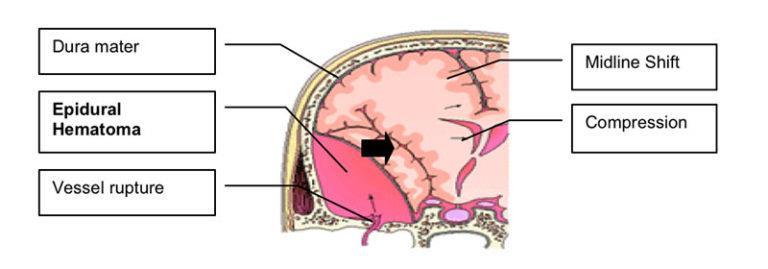

Are bleeding in and around the brain caused by a burst blood vessel. Different types of hematomas form depending on where the blood collects in the protective membranes surrounding the brain, which include the dura mater, arachnoid and pia mater

• Epidural hematomas

• Subdural hematomas

• Subarachnoid hemorrhage

• Intracerebral hematoma

- Epidural hematomas involve bleeding into the area between the skull and the dura mater. These can occur within minutes to hours after injury and are particularly dangerous - Subdural hematomas involve bleeding between the dura and the arachnoid mater, and, like epidural hematomas, exert pressure on the outside of the brain (common in older adults after a fall)

- Subarachnoid hemorrhage is bleeding between the arachnoid mater and the pia mater.

- Intracerebral hematoma involves bleeding into the brain itself and damages the surrounding tissue.

Bone Fractures

Subgaleal Hematoma

Epidural hematomas

Subarachnoid

Hemorrhage